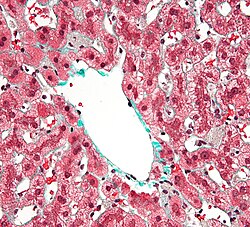

Qaraciyər mürəkkəb borulu vəzilərdən olub, bir çox paycıqlardan – lat. lobuli hepatis ibarətdir. Paycıqları təşkil edən atmalar qaraciyər epitel hüceyrələrindən əmələ gəlmişdir. Qaraciyər paycıqları şəkilcə çoxbucaqlı olub, bir-biri ilə birləşdirici toxuma vasitəsilə birləşmişdir. Paycıqların daxilində retikulyar liflərdən təşkil olunmuş tor vardır; bu liflər, ehtimal ki, qaraciyər kapillyarları endotelinin törəmələridir. Həmin endotel faqositoz vəzifəsinə malik ulduzabənzər (Kupfer adlanan) hüceyrələrdən ibarətdir.